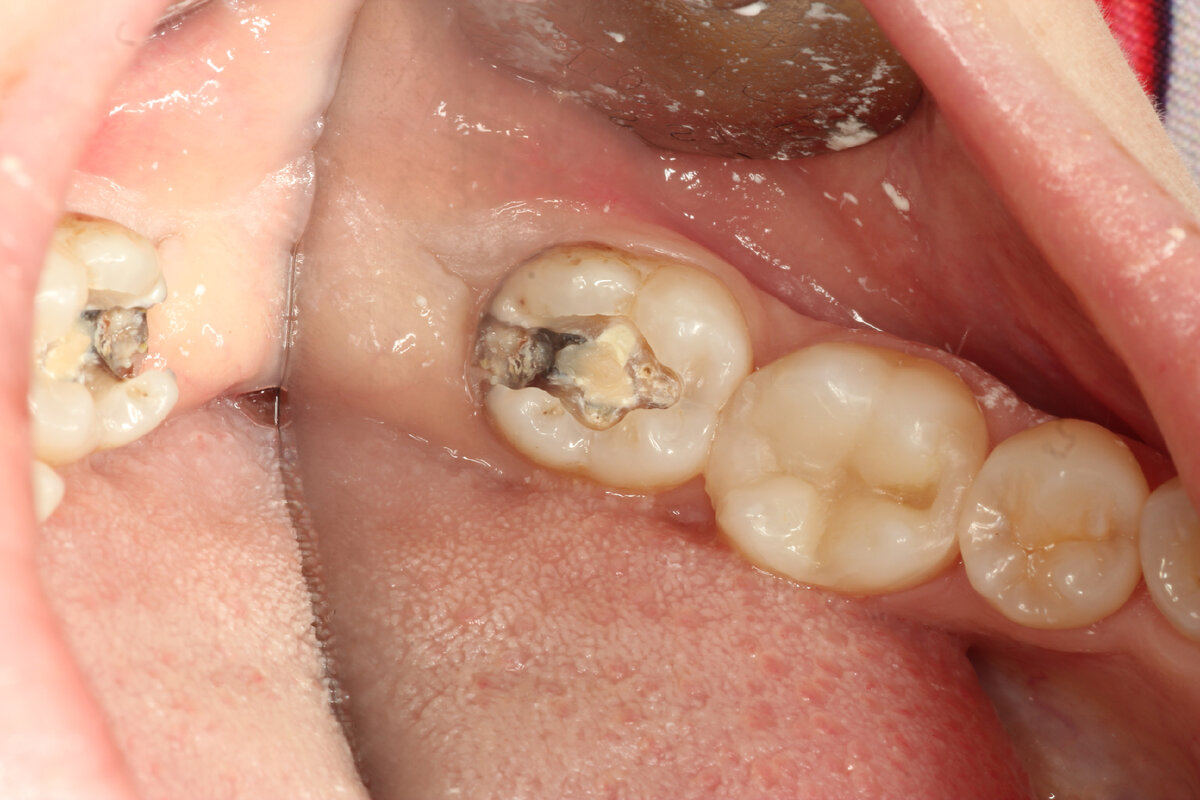

Пациент пришел на проф. осмотр, видим такую картину. Самое интересное, что его абсолютно ничего не беспокоит. Сегодня покажу семерку (последний зуб)

Промежуточный этап, вся задняя часть зуба в кариесе